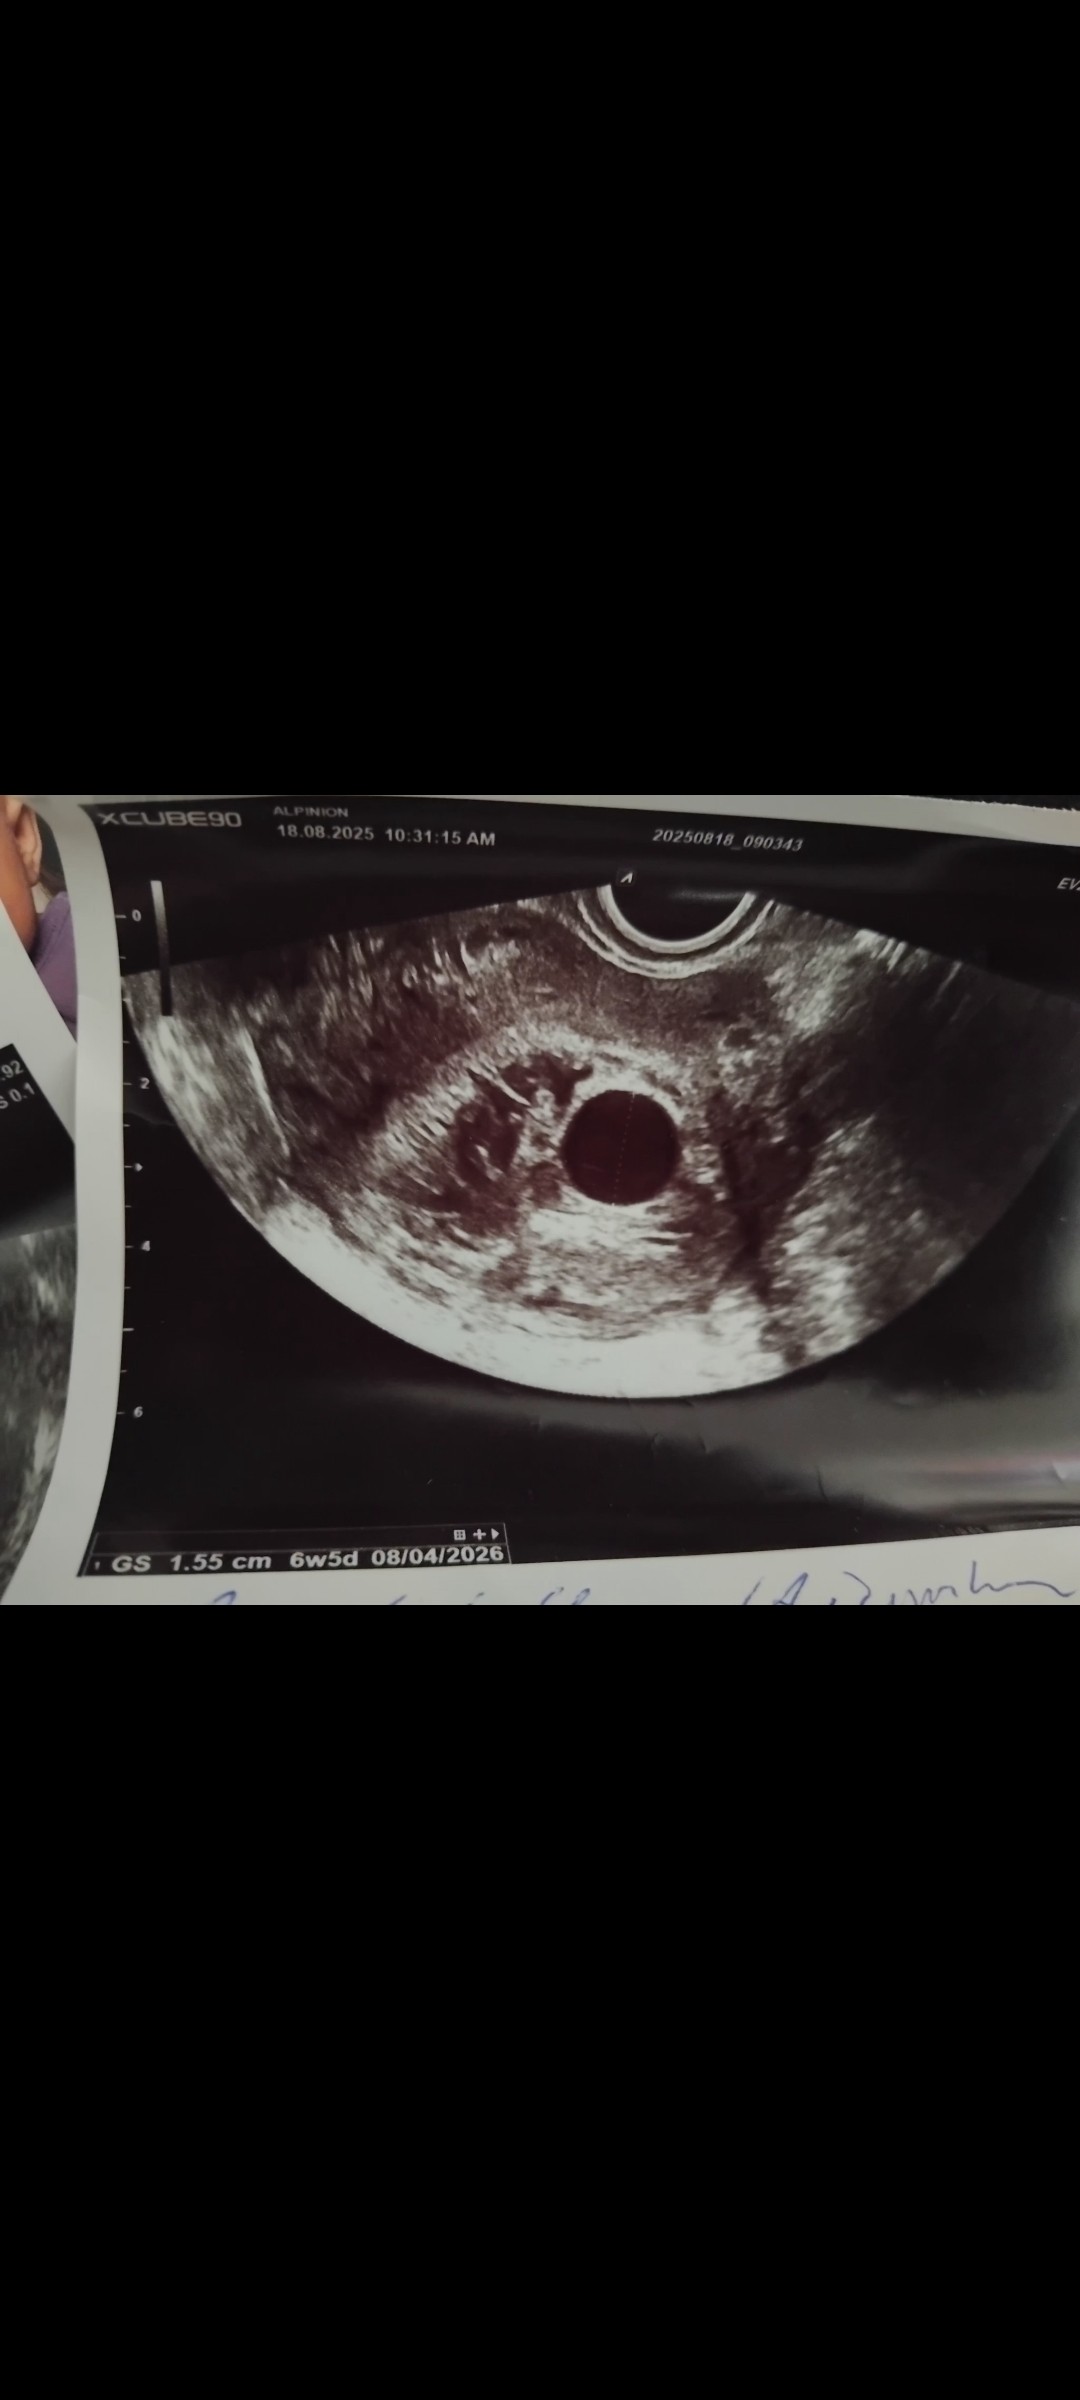

18 sierpnia miałam kolejna wizytę pecherzyk urósł do 1.55 niestety zarodka Dalej Brak